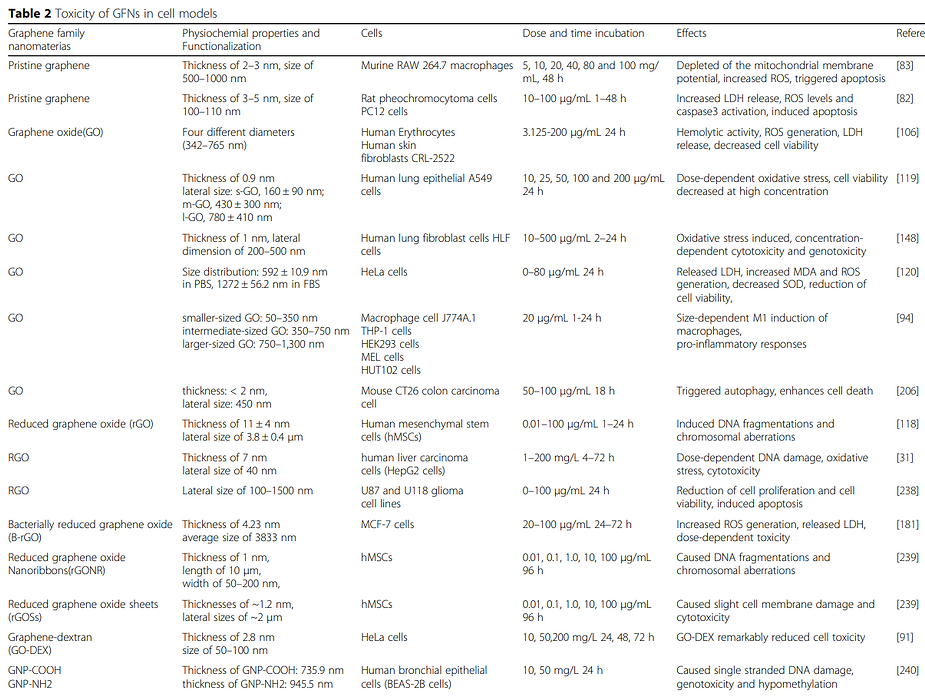

Toxicity of Graphene Family Nanomaterials

Toxicity of Graphene Family of Nanomaterials

Toxicity of Graphene Family of Nanomaterials in Cell Models

Toxicity of Graphene of Family of Nanomaterials in Cell Models

Graphene Family Nano-materials trigger local and systemic toxic effects, induce genotoxicity in vitro and in vivo, alter the gut microbiome, cause genetic mutations, and are inedible. Further toxicological and risk assessment studies are needed especially when used in food or injections of any type.

Graphene, Graphene Oxide (GO), carbon nano-tubes, and the entire graphene-family nano-materials (GFN) are toxic in almost all their forms, causing mutagenesis (cancer, chromosomal alteration), cell death, apoptosis, necrosis, and the release of free radicals.

Several typical mechanisms underlying Graphene Oxide nano-material’s toxicity have been revealed in numerous studies including my own, for instance, physical destruction, oxidative stress, DNA damage, inflammatory response, apoptosis, autophagy, and necrosis. In these mechanisms, toll-like receptors, transforming growth factor-beta (TGF-β) and tumor necrosis factor-alpha (TNF-α) dependent-pathways are involved in the signaling pathway network, and oxidative stress plays a crucial role in these pathways.

Many experiments have shown that Graphene Oxide nano-materials have toxic side effects in many biological applications.

According to the USA FDA, graphene, Graphene Oxide, and reduced graphene oxide elicit toxic effects both in vitro and in vivo.

Graphene-family nano-materials (GFN) are not approved by the USA FDA for human consumption.